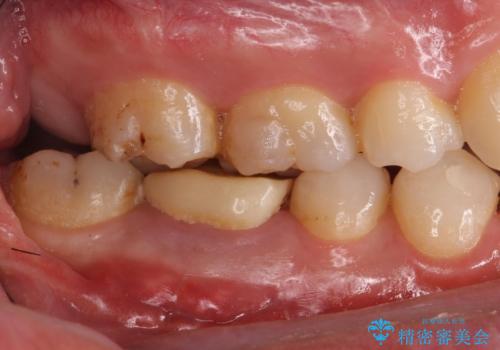

- 右下の奥歯がうずくとのことで来院されました。

根管治療を行った後、セラミックのかぶせ物を装着します。